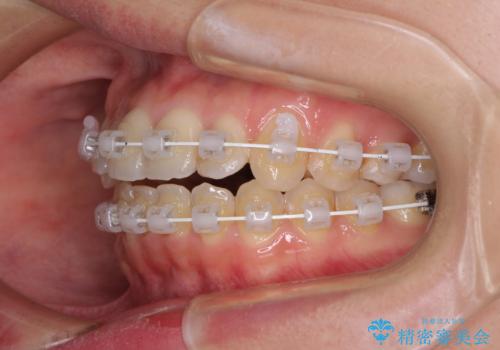

- 矯正装置

- 審美装置

- 前歯のデコボコを気にして来院された患者様です。

上顎右側犬歯が八重歯になっており、それによって奥歯が前方に移動しているため、右側の咬み合わせの改善が必要と判断されました。

マウスピース矯正では改善に時間がかかる、あるいは改善しきれない可能性があることを伝えたところ、短期間で確実に治療ができるワイヤー矯正を選択されました。

より治療を速やかに行うため、上顎右側にアンカースクリューを使用し、目標としていた1年半ほどで治療を終えることができました。